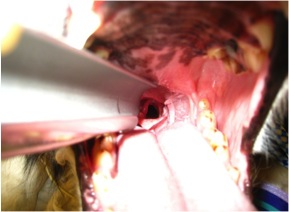

Below is a video demonstrating laryngeal paralysis. The laryngeal opening can be seen and you will notice that it is not moving much at all during the phases of breathing.

Below is a picture of an arytenoid lateralization. Notice the difference on the opening from the previous video.